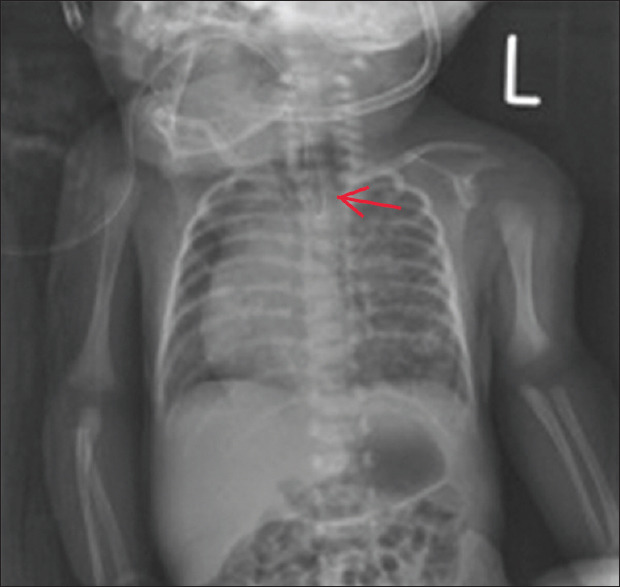

Congenital pulmonary airway malformation (CPAM) together with oesophageal atresia and tracheoesophageal fistula (TOF) is a very rare condition in neonates. We presented a case of an infant with Gross type C oesophageal atresia with TOF coexisting with Stocker Type III CPAM in our centre. It is interesting to know that TOF associated with type III CPAM has never been reported in the literature. The child was delivered through caesarean section, and because of respiratory distress post-delivery, endotracheal intubation was carried out immediately. CPAM was diagnosed by a suspicious finding from the initial chest X-ray and the diagnosis was confirmed through computed tomography scan of the chest. The patient was initially stabilised in a neonatal intensive care unit (NICU), and after the successful ligation of fistula and surgical repair of TOF, lung recruitment was started by high flow oscillatory ventilation. The patient recovered well without complications and able to maintain good saturation without oxygen support through the stay in the neonatal unit. Early recognition of this rare association is essential for immediate transfer to NICU, the intervention of any early life-threatening complications, and for vigilant monitoring in the postoperative period.